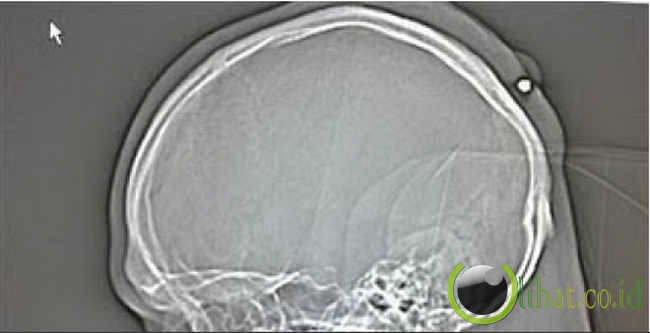

2. Tertembak di kepala dan baru tahu lima tahun kemudian

[lihat.co.id] - Seorang lelaki Jerman tidak disebutkan namanya ternyata tidak mengetahui jika dia telah tertembak di kepala pada malam tahun baru 2004 sebab sangat mabuk.

Lelaki itu baru menyadari sebuah peluru kaliber 0,22 tertanam di kepala pada 2009. Itu pun secara tidak sengaja saat dirinya pergi ke dokter dengan keluhan perut.

Dia mengakui pada malam itu seperti terhantam benda berat di kepala. Namun dia pikir bukan sesuatu yang berarti.